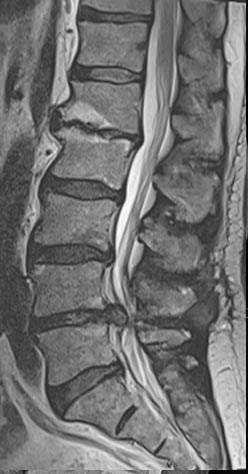

44 year old man with severe low back pain with intermittent radiation of the pain down the right leg. After undergoing conservative treatment, continued to have debilitating pain. MRI revealed a right paracentral disc herniation but CT scan revealed a unilateral pars fracture. After debating on microdiscectomy vs fusion, patient elected to undergo lumbar fusion. 4 months postop patient returned to surfing again. 9 months postop patient wrote “My recovery continues to do very well and we just got back from 8 days camping which including mountain biking, hiking, and a lot of work. Surfing almost every day and life is good…you have helped get my life and my families life back to normal.”

After procedure.